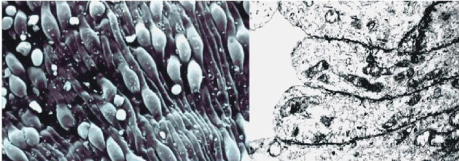

Figure 7: Wall of the spleen sinuses formed by endothelial cells that totally cover its surface without any type of junction. Right: Cross-section observed with Transmission Electron Microscopy (TEM); Left: Three dimensional views observed with Scanning Electron Microscopy (SEM).

Figure 8: Passage of RBCs through the Inter-Endothelial Slots (IES) of the spleen filter. A marked deformation is appreciated by both three-dimensional view with SEM (above) and cross-section with TEM (below). The arrows indicate the RBCs passing through the narrow IES.

그림 7: 비장 정현동 벽은 어떠한 접합 없이 표면을 완전히 덮는 내피 세포로 형성. 오른쪽: 투과전자현미경(TEM)으로 관찰된 단면; 왼쪽: 주사전자현미경(SEM)으로 관찰된 3차원 뷰.

그림 8: 비장 필터의 세포간 내피 슬롯(IES)을 통과하는 RBC. SEM의 3차원 뷰(위)와 TEM의 단면(아래) 모두에서 뚜렷한 변형이 관찰됨. 화살표는 좁은 IES를 통과하는 RBC를 나타냄.